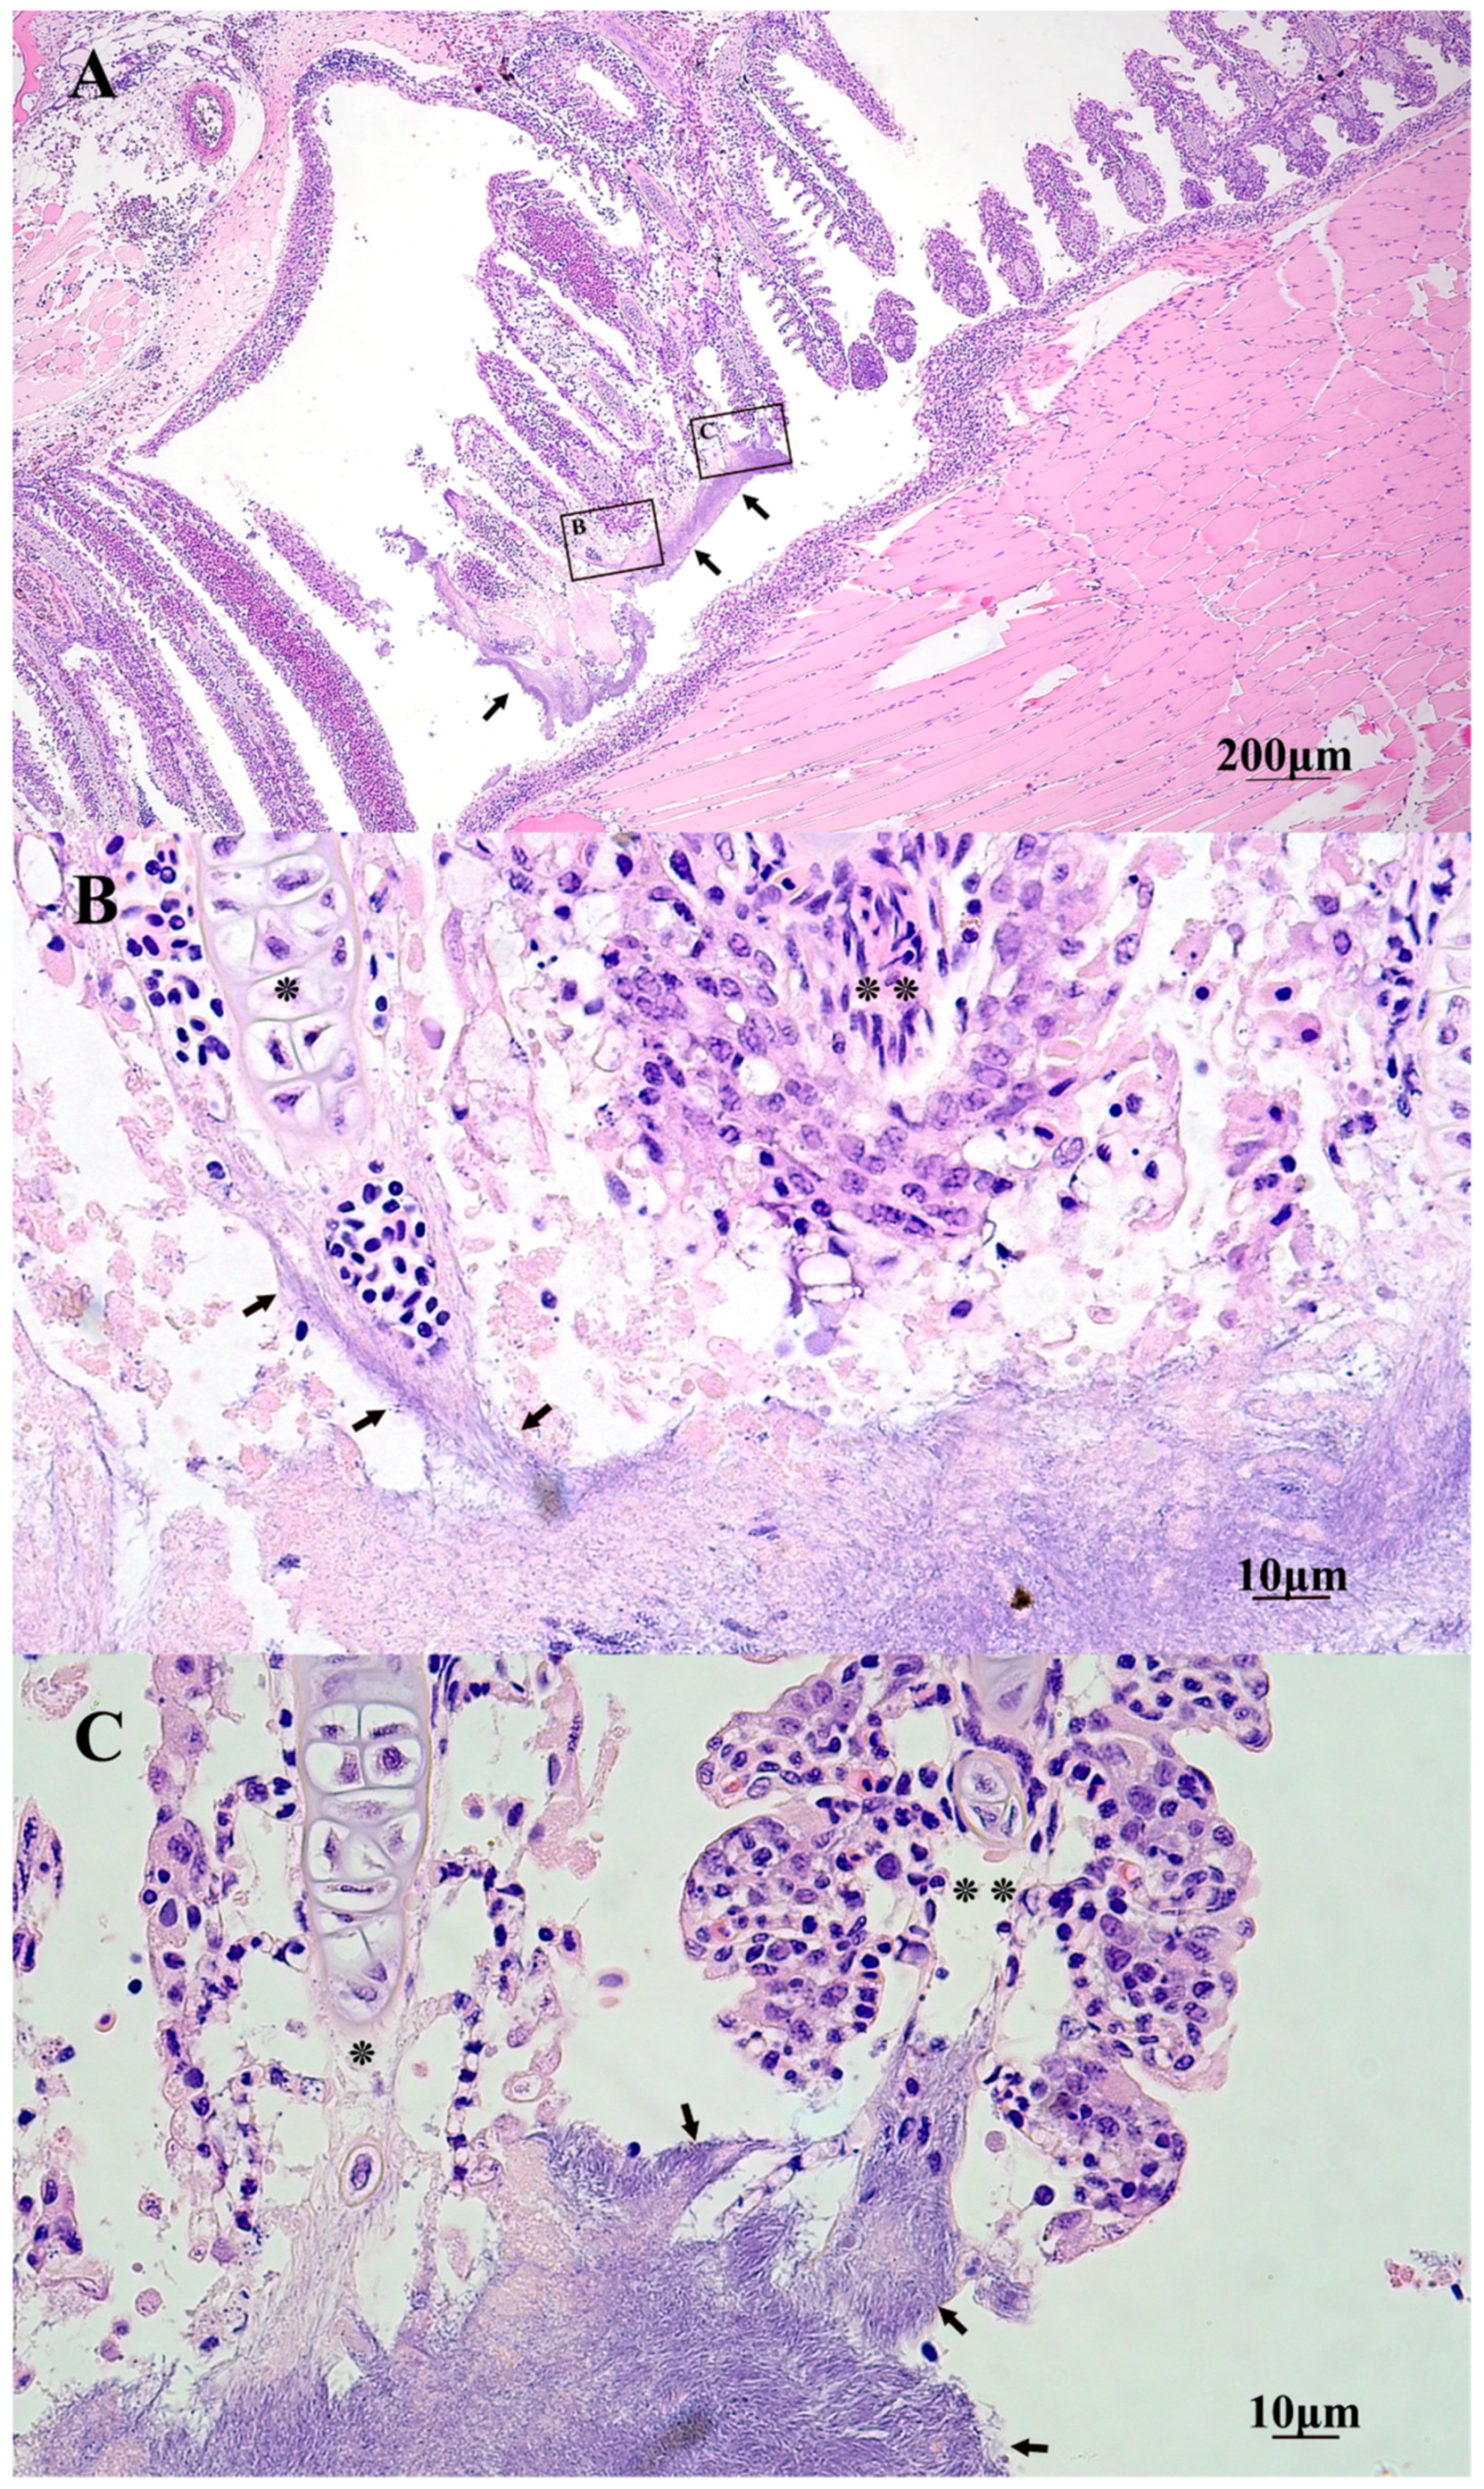

2.5. Gross and Histopathology